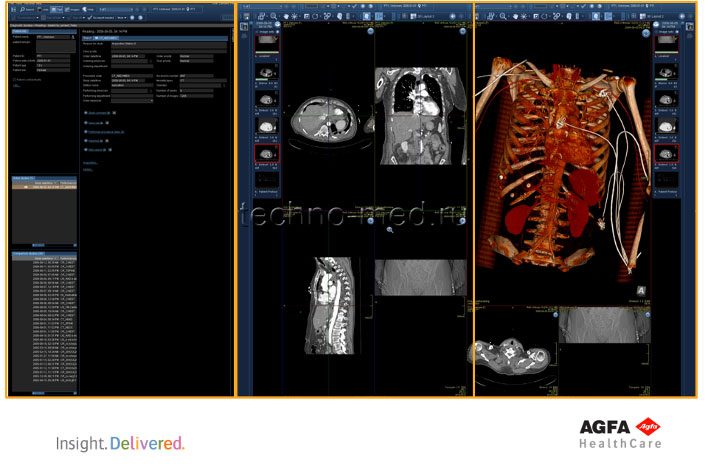

- Поддерживает непрерывный поток операций с изображениями во всех подразделениях предприятия;

- Обеспечивает действие механизма реализации рабочих процессов, основанных на поставленных задачах, соответствующий современным сложным требованиям;